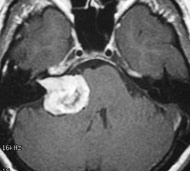

Процедуры визуализации. Магнитно-резонансная томография (МРТ) обычно применяется для постановки диагноза при опухолях головного мозга. Во время МРТ используются магнитные поля и радиоволны, которые генерируют изображение головного мозга. В некоторых случаях в вену руки вводится контрастное вещество до начала проведения МРТ. Несколько специальных изображений МРТ могут помочь врачу оценить ситуацию и назначить план лечения, включая проведение функциональной МРТ, перфузионной МРТ и магнитно-резонансной спектроскопии.

Операция

Если опухоль головного мозга расположена в месте, доступном для проведения операции, хирург постарается удалить всю опухоль настолько, насколько это возможно. В некоторых случаях опухоли являются небольшими по размеру и их можно легко отделить от окружающей головной мозг ткани, что делает операцию по полному удалению опухоли оправданной. В других случаях опухоли расположены около чувствительных зон в головном мозге, что делает операцию рискованной. В таких случаях врач может попытаться удалить опухоль настолько, насколько это безопасно. Удаление даже части опухоли головного мозга может помочь ослабить признаки и симптомы заболевания. В некоторых случаях берется лишь небольшая биопсия для подтверждения диагноза.